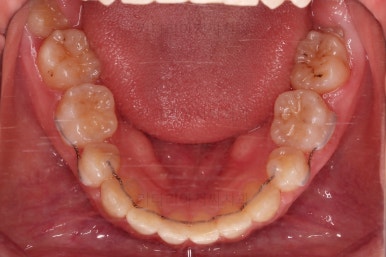

부산연산동교정치과 치료 종료 시의 모습이에요.

삐뚤한 치열도 가지런해졌고 2급 부정교합도 정상교합으로 맞춰졌어요.

튀어나와있던 앞니도 좋아졌고, 과개교합도 개선이 되었어요.

옆라인도 좋아졌고 입술을 다무는 느낌이 굉장히 편안해져서 입이 많이 들어간 건 아닌듯하지만 얼굴모습은 매우 좋아졌어요.

교합이나 치아배열의 모습도 좋아졌고요.